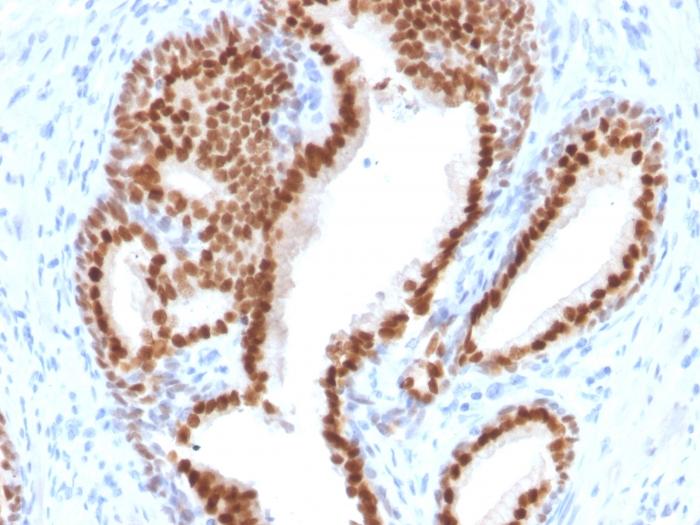

NKX3. 1 is a prostate specific gene encoding a transcription factor that plays an important role in normal prostate development and carcinogenesis. It is a prostatic tumor suppressor gene located on chromosome 8p21. 2, which frequently undergoes a loss of heterozygosity. NKX3. 1 expression is highly restricted in prostate epithelial cells and therefore can be used as a diagnostic biomarker for prostate cancer and other metastatic lesions of prostatic origin. Furthermore, NKX3. 1 shows better sensitivity than Prostate Specific Antigen (PSA) for identifying metastatic prostatic adenocarcinoma. This suggests that immunohistochemical staining of NKX3. 1, along with other prostate-restricted markers, may be valuable for the definitive determination of prostatic origin in poorly differentiated metastatic carcinomas. Primary antibodies are available purified, or with a selection of fluorescent CF® Dyes and other labels. CF® Dyes offer exceptional brightness and photostability. Note: Conjugates of blue fluorescent dyes like CF®405S and CF®405M are not recommended for detecting low abundance targets, because blue dyes have lower fluorescence and can give higher non-specific background than other dye colors.

Positive Control

Highly expressed in the prostate and at a lower level in the testis.

Antibody target cellular localization

Nucleus

Tumor expression

Prostate cancer